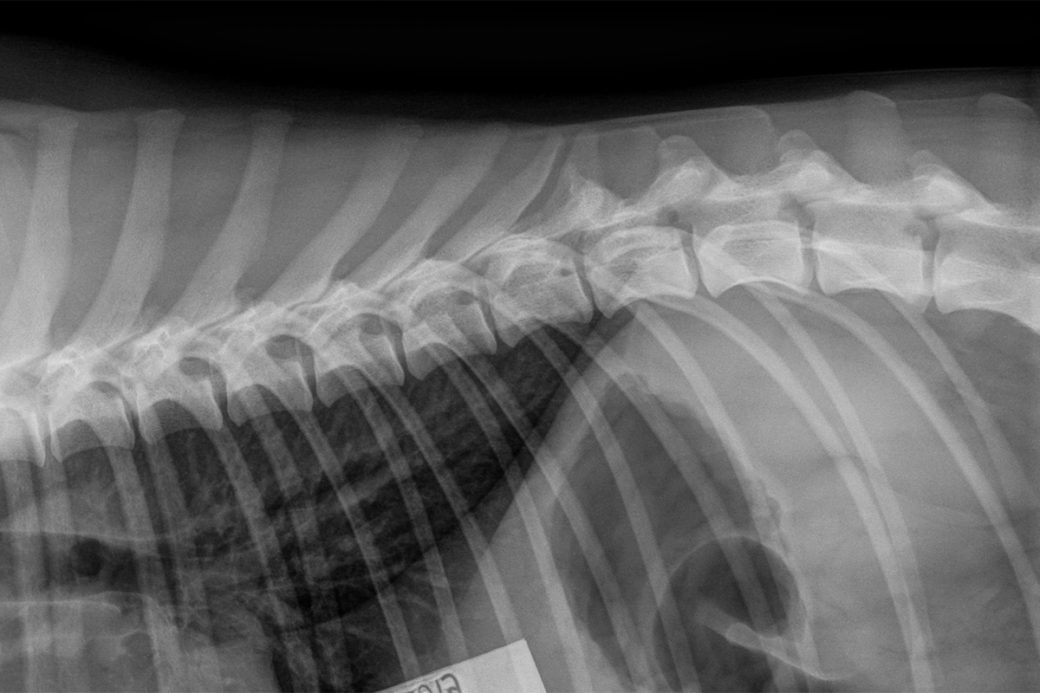

Selkä LTV0 & VA1 (viimeisessä rintanikamassa vaillinaisesti kehittyneet kylkiluut)